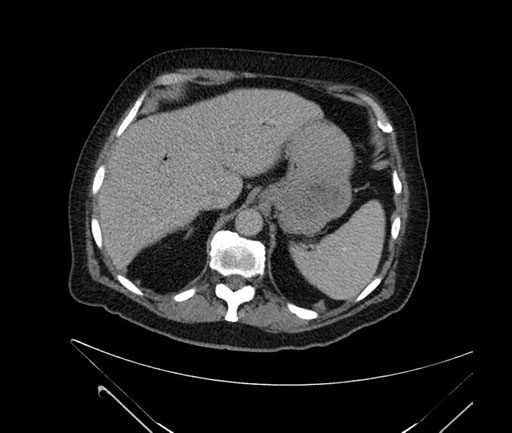

Whipple (pancreaticoduodenectomy) [case 7]

Imaging Analysis

Look through the patient's CT scan to identify any areas of concern for the necessary procedure.

Based on your CT findings, which issue(s) would give reason for "planned slowing down moment(s)" in this case?

Considering a standard Whipple procedure, what step(s) of the operation would you do differently in this case?